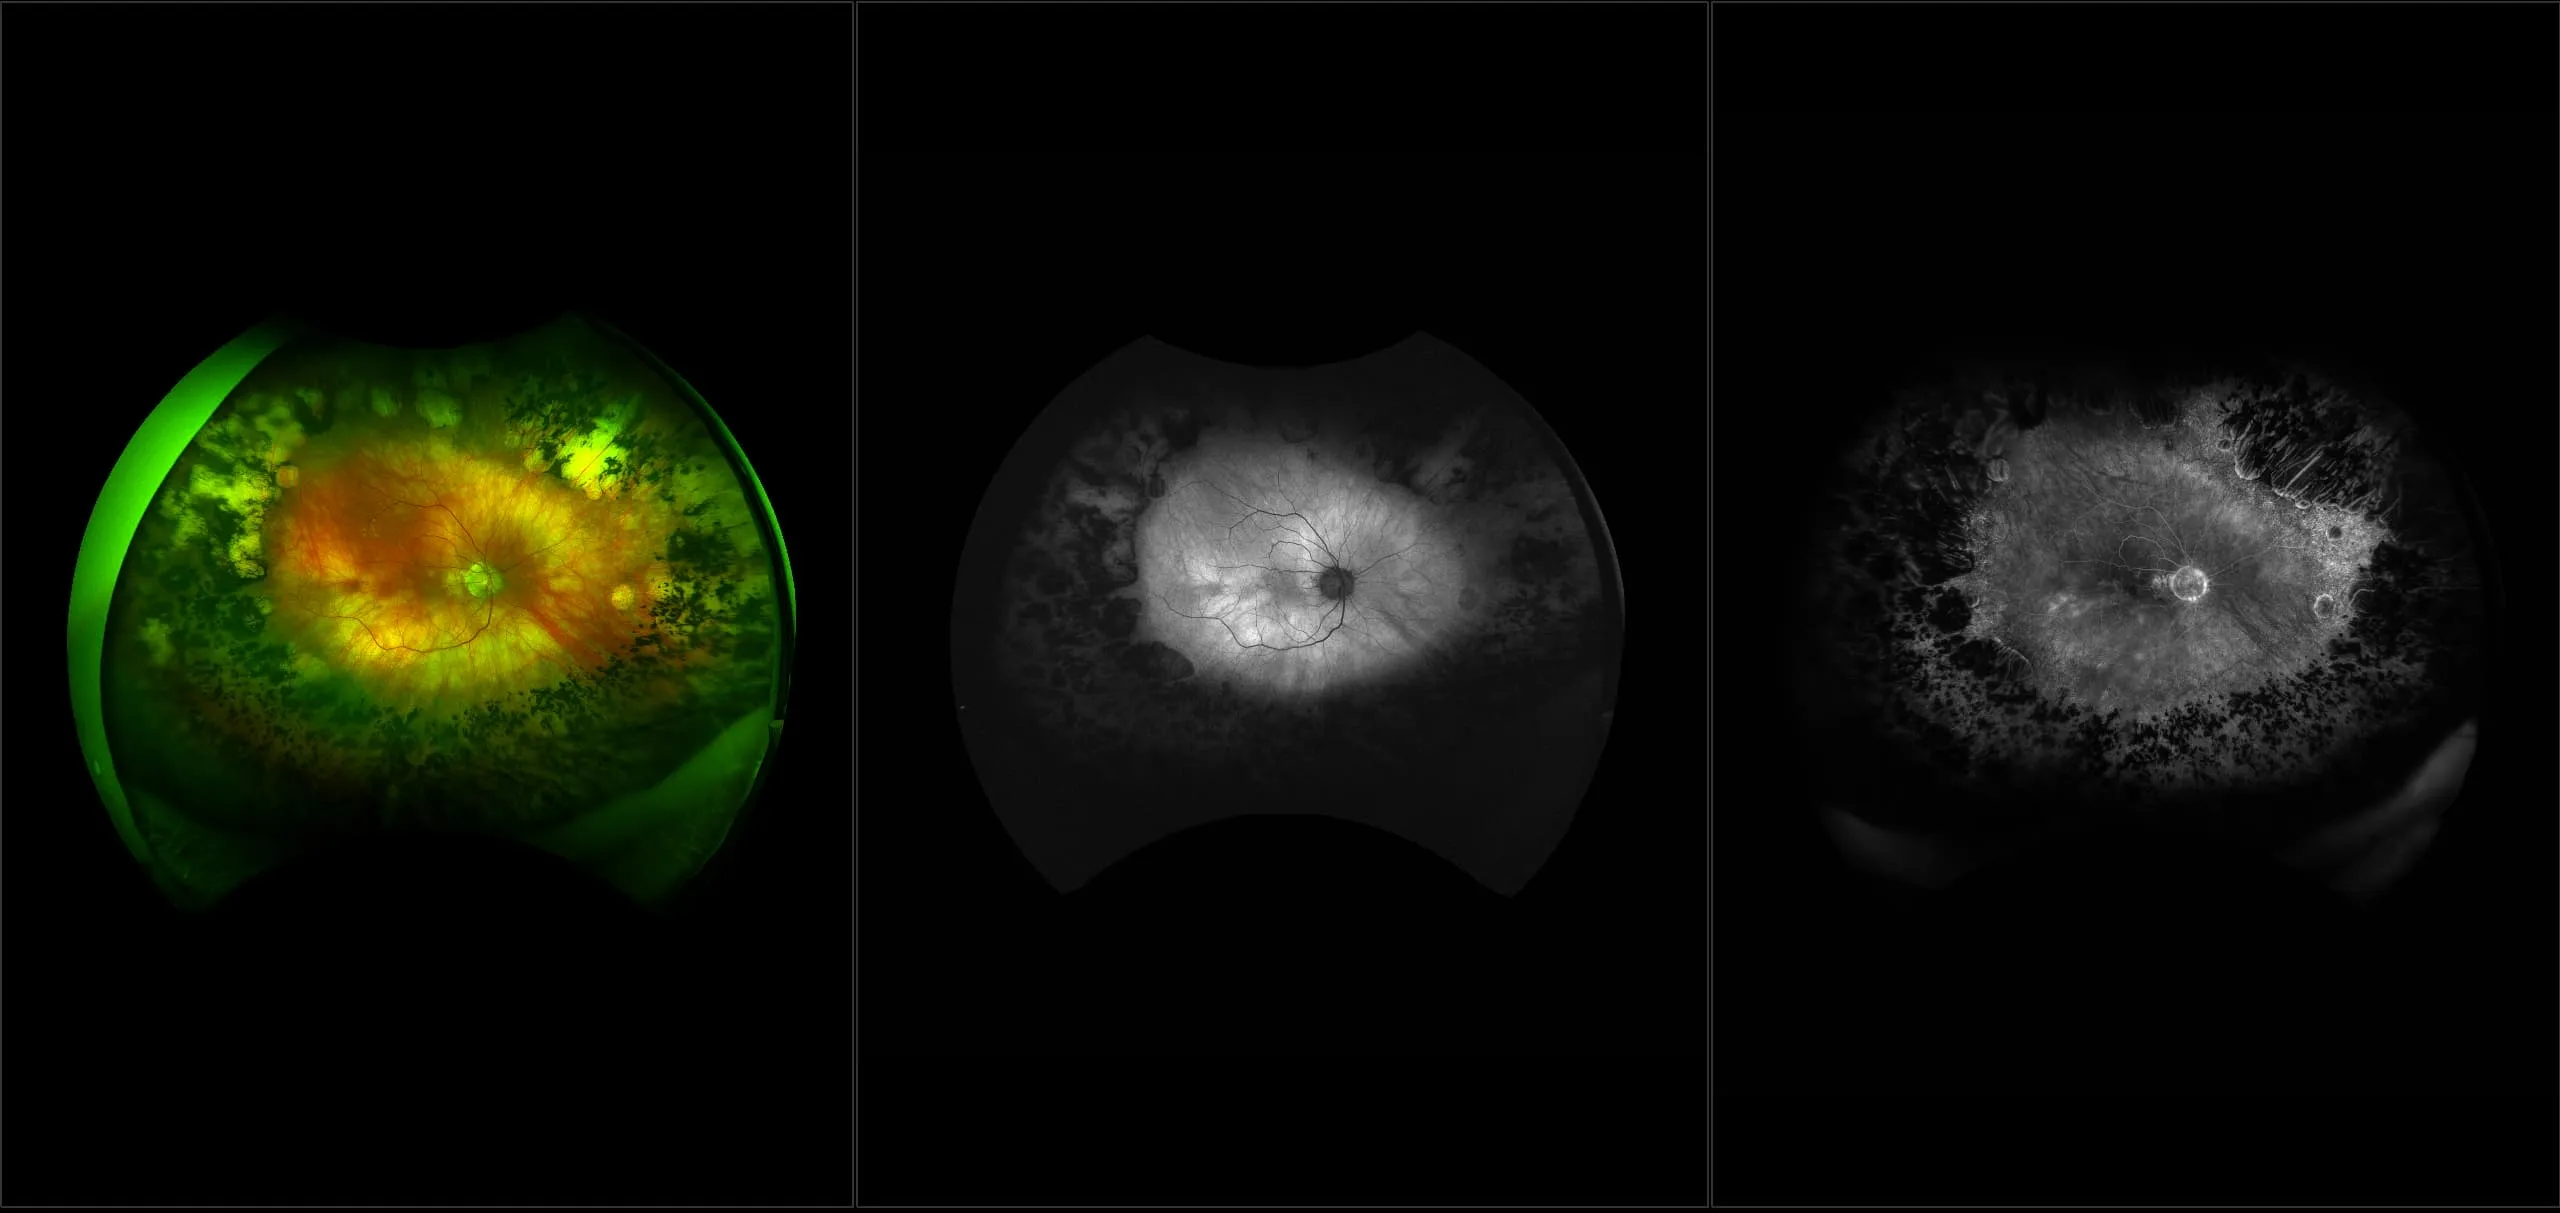

This material is designed as a searchable reference resource to support clinical decision-making. The information contained here should be used as general guidance when viewing optomap and OCT images from Optos devices. The differential diagnosis should be made under the direction of the responsible physician. These images were taken on the latest ultra-widefield optomap devices.

optomap Recognizing Pathology is searchable by pathology and/or optomap image modality. You may search by multiples of each selection. Each individual case is represented by the accompanying thumbnail image. Most cases include several different optomap image modalities. To view a full description of the case, please click on the thumbnail. Each image in the case will be made available through our OptosAdvance software which provides multi-dimensional visualization of digital images to aid in the analysis of anatomy and pathology. Support and pathology definitions can be found by selecting one of the buttons, above. Should you have questions, please complete the form below.